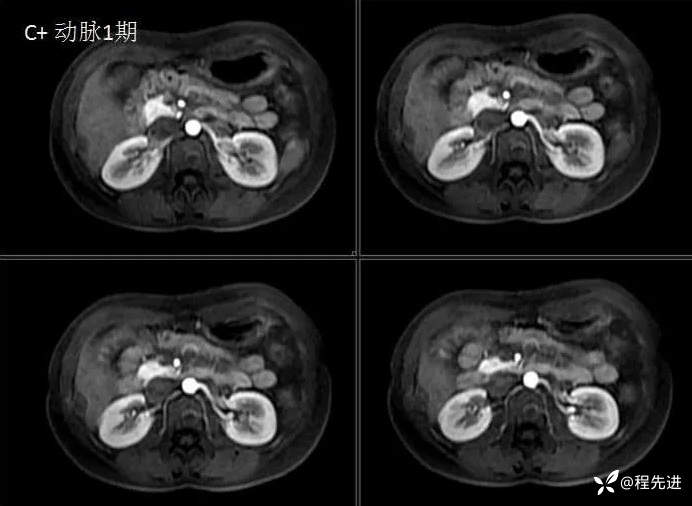

MRI检查: